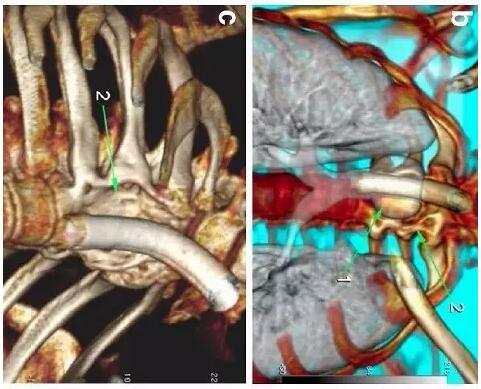

胸部CT顯示氣切套管氣囊周圍氣管擴(kuò)張,胸1-4椎體前部受到侵蝕(下圖a-c)。

下圖箭頭1為氣切套管氣囊緊貼T1-4椎體水平,造成椎體前部受到侵蝕(箭頭2):

作者推測(cè)患者骨質(zhì)吸收、骨髓炎與氣切套管氣囊過度膨脹有關(guān),為氣囊過度膨脹造成椎體血流灌注降低所致。在我院住院期間,我們也發(fā)現(xiàn)高氣囊壓力才能防止漏氣。經(jīng)食道內(nèi)鏡檢查未發(fā)現(xiàn)氣管食管瘺。